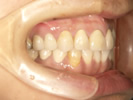

50代女性

![]() |

治療前 |

||

治療中。仮歯。 左上の奥にインプラント埋入。 噛みあわせ治療を行いました |

治療後 全体の歯で食事がおいしくできるようになったと喜んでおられました。 |